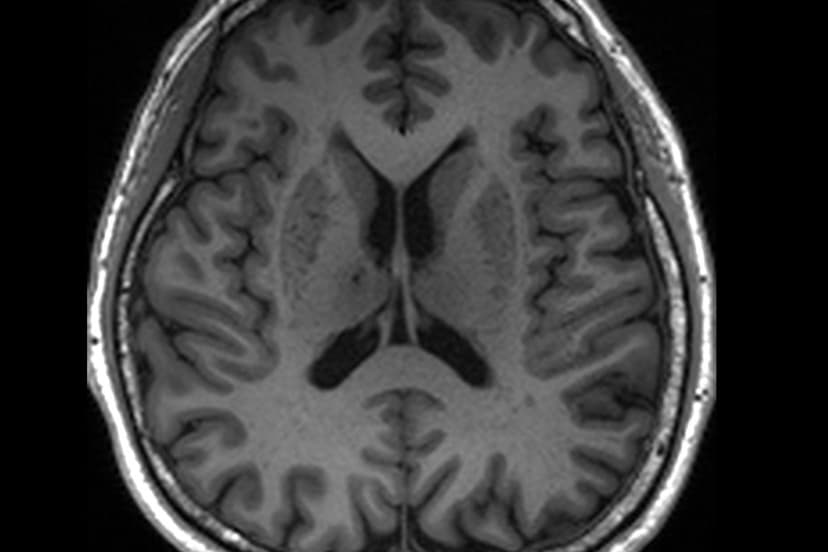

Researchers have identified potential early warning signs for Alzheimer's disease by examining MRI scans for blockages in the brain's natural drainage system. These natural "drains," which clear harmful waste, can become clogged, leading to enlarged perivascular spaces detectable on routine MRI scans. This finding suggests that anomalies in these spaces could serve as crucial predictors of dementia, even before substantial brain damage occurs.

The study, involving nearly 1,000 participants in Singapore, observed that individuals with mild cognitive impairment were more likely to exhibit these clogged drains compared to those without cognitive concerns. The presence of enlarged perivascular spaces was also found to correlate with certain blood markers associated with Alzheimer's, such as amyloid plaques and tau tangles.